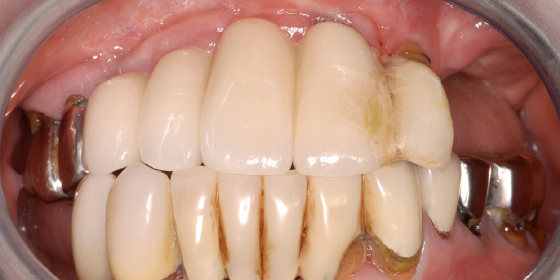

すべてのインプラントが骨と結合しているのを確認しました。前医が治療した上顎前歯のブリッジは取り外し、今回埋めたインプラントと連結することにしました。

最終補綴物装着